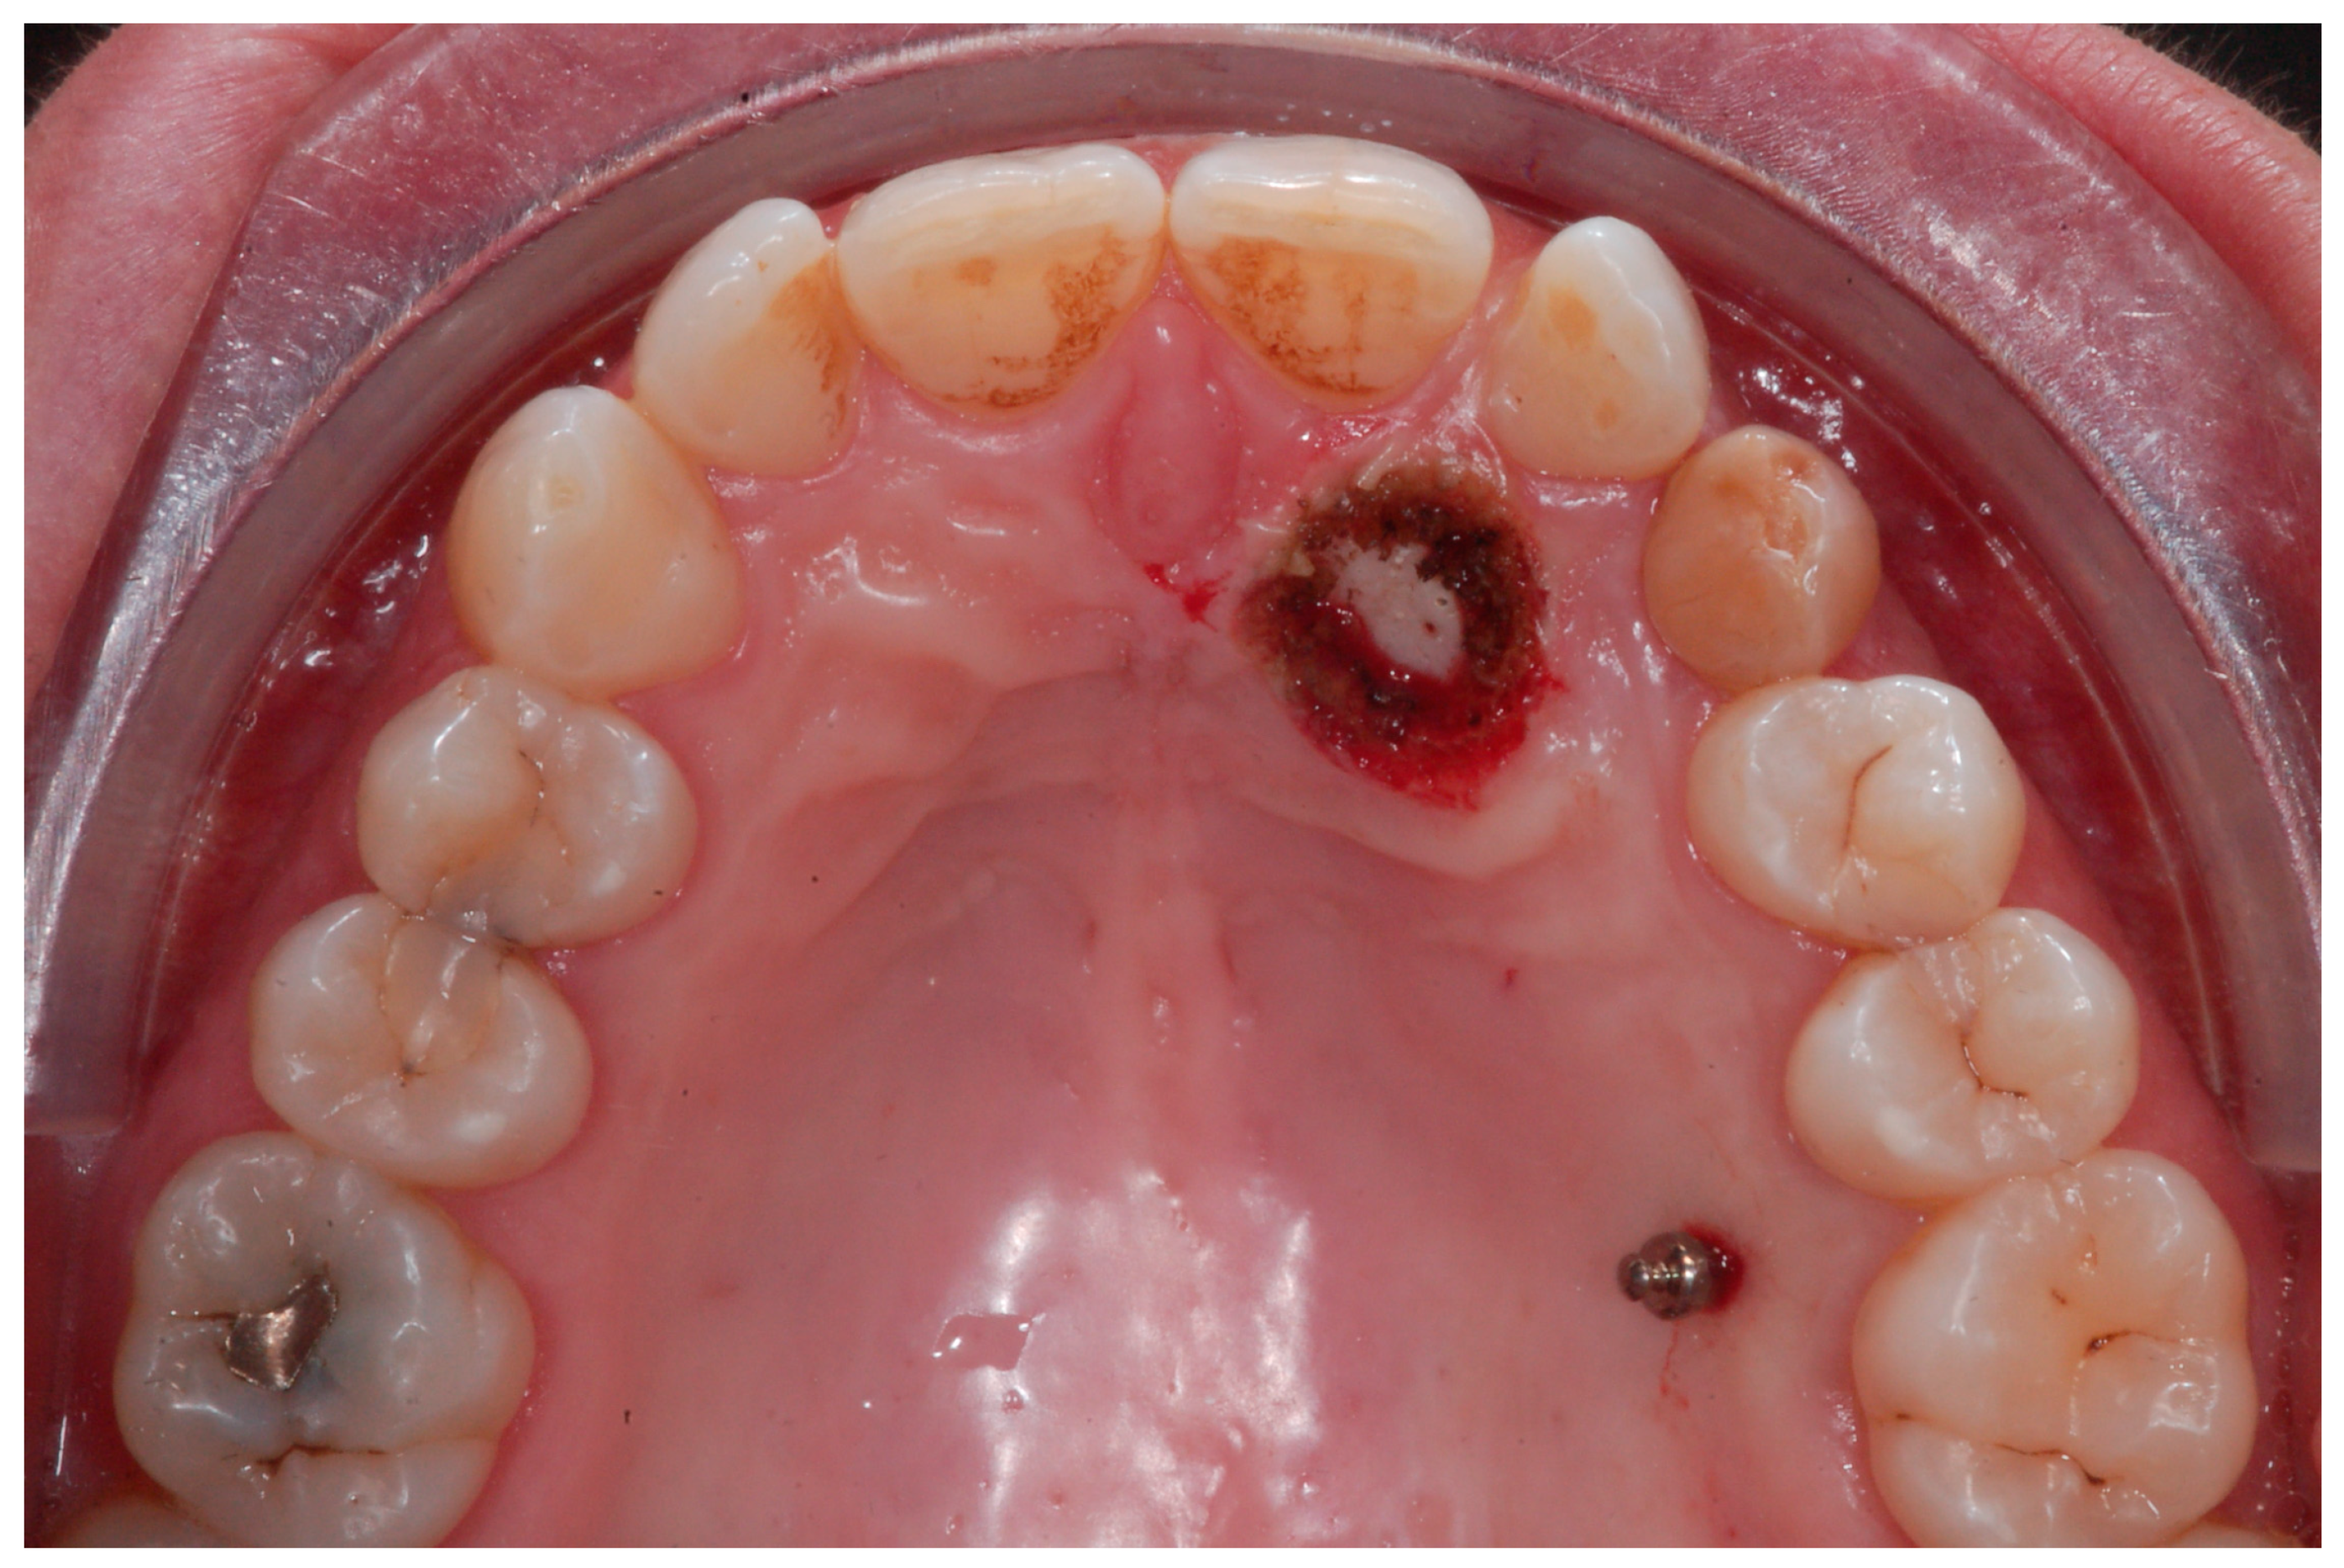

An adult female patient, 43 years old, with Class I occlusion on both sides and with a slight deep bite, light crowding, a persistent deciduous canine no. 63, and a horizontally impacted canine with the crown tip close to the lateral incisors and the tip of the root protruding beyond the buccal bone in the 2.3 area is presented in Figure 9 and Figure 10.

Figure 9.

Class I occlusion on both sides with a slight deep bite, light crowding, a persistent deciduous canine no. 63, and a horizontally impacted canine with the tip of the crown close to the lateral incisors and the tip of the root protruding beyond the buccal bone in the 2.3 area.

Figure 10.

CBCT pictures of the patient. Since the patient was subjected to periodic radiographic control as she was a cancer survivor, the decision was to do a CBCT to receive all the informations useful for the deimpaction treatment and avoid conventional orthodontic X-rays like panoramic and lateral X-rays.